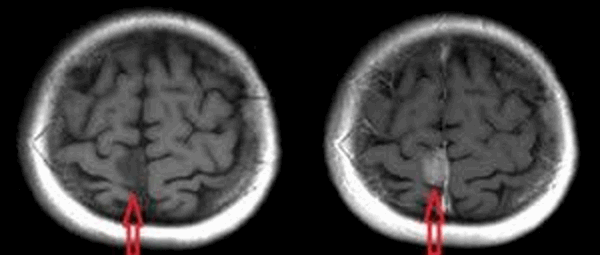

Разница в визуализации при МРТ с контрастным веществом

Что показывает МРТ головного мозга с контрастом

МРТ головного мозга с контрастом или без

Разница между процедурами — это информативность снимка, ведь применение контраста позволяет детально рассмотреть исследуемый патологический очаг. Стандартное МРТ проводят без усиливающих эффект веществ. Перед обычной процедурой подготовка не происходит.